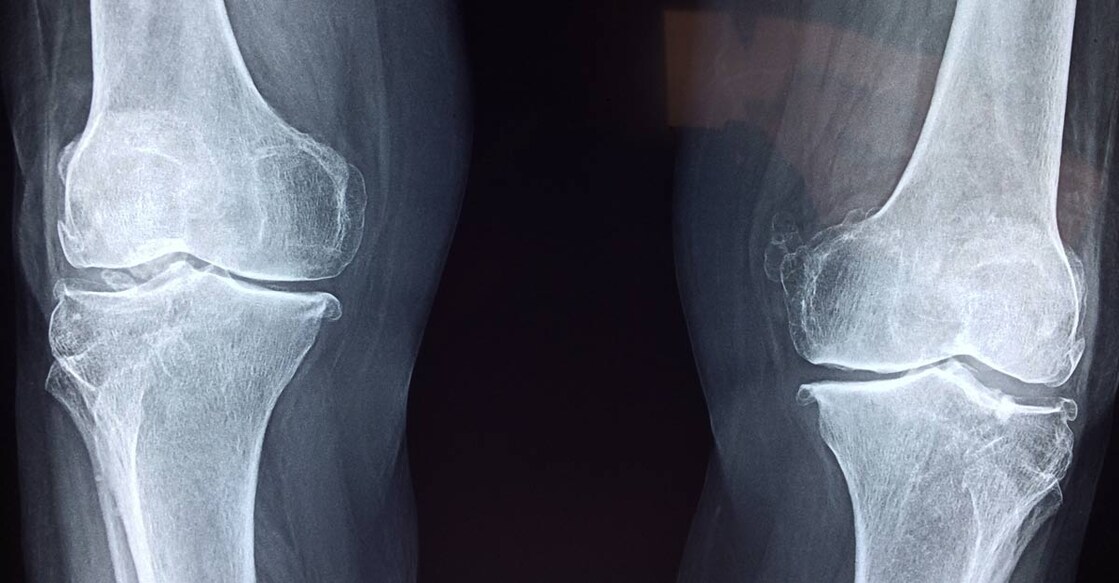

The surgery, named high tibial osteotomy, is a knee surgery aimed at younger patients in the earlier stages of knee osteoarthritis, according to the study published in CMAJ (Canadian Medical Association Journal).

Knee osteoarthritis is a common cause of pain and disability and puts tremendous burden on health care systems. Total knee replacement is frequently performed on older patients with end-stage disease and limited mobility.

Of the patients in this study getting high tibial osteotomy (643 knees in 556 patients), 95 per cent did not need a total knee replacement within 5 years, and 79 per cent did not get a total knee replacement within 10 years.

Even in patients traditionally not considered ideal candidates for high tibial osteotomy (e.g., women and patients with later-stage disease), about 70 per cent did not get a knee replacement within 10 years.

The procedure is particularly suitable for people who are younger, have less severe joint damage and who may be more physically active.